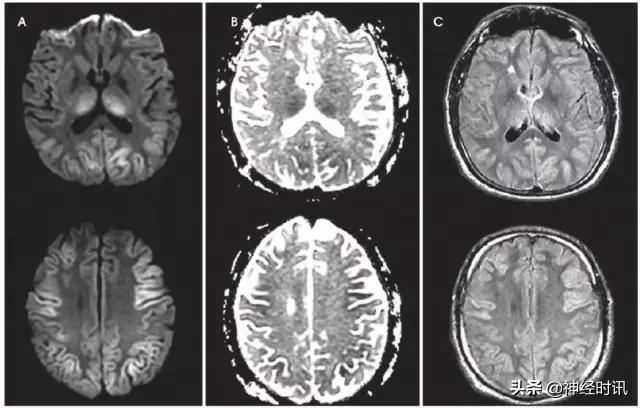

癫 痫

三分之一的卒中类似疾病是由于癫痫发作或发作后功能障碍导致。有时癫痫也可导致弥散受限(图2)。其分布特点不符合血管分布,水肿和脑回增强出现更早,脑灌注正常或增加,无血管闭塞,有时同时有皮层弥散受限和皮层下弥散增加。

图2 一例66岁男性,癫痫发作伴意识状态改变、急性失语和右侧凝视,拟诊脑卒中并给予IV-tPA治疗。左侧病灶情况下的右侧凝视可提示癫痫发作。他的入院MRI显示左侧额顶叶皮层和皮层下白质弥散受限(A和B)和水肿(C)。他的症状和影像学(图像未提供)显示在出院前完全缓解。